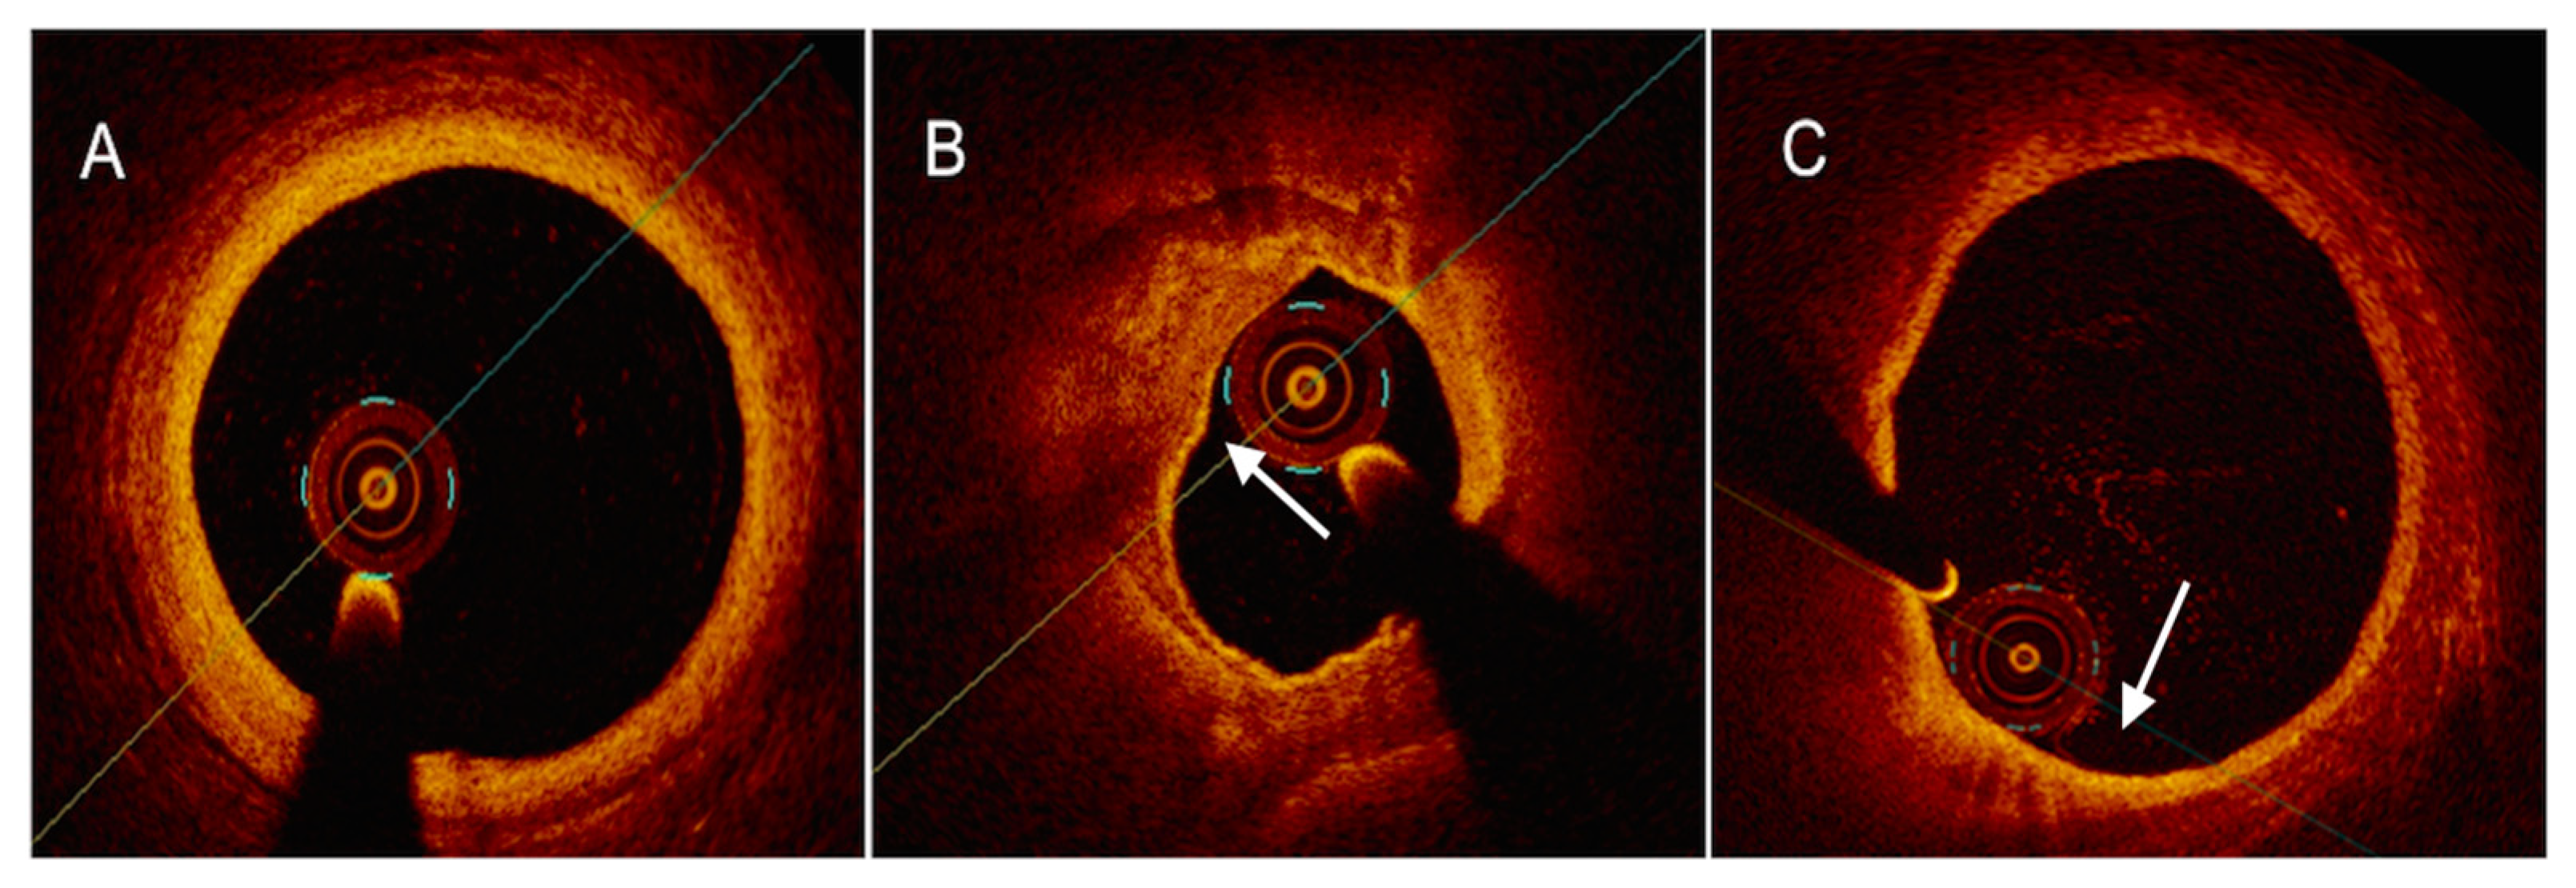

- Terada, K.; Kubo, T.; Kameyama, T.; Matsuo, Y.; Ino, Y.; Emori, H.; Higashioka, D.; Katayama, Y.; Khalifa, A.K.M.; Takahata, M.; et al. NIRS-IVUS for Differentiating Coronary Plaque Rupture, Erosion, and Calcified Nodule in Acute Myocardial Infarction. JACC Cardiovasc. Imaging 2021, 14, 1440–1450. [Google Scholar] [CrossRef] [PubMed]